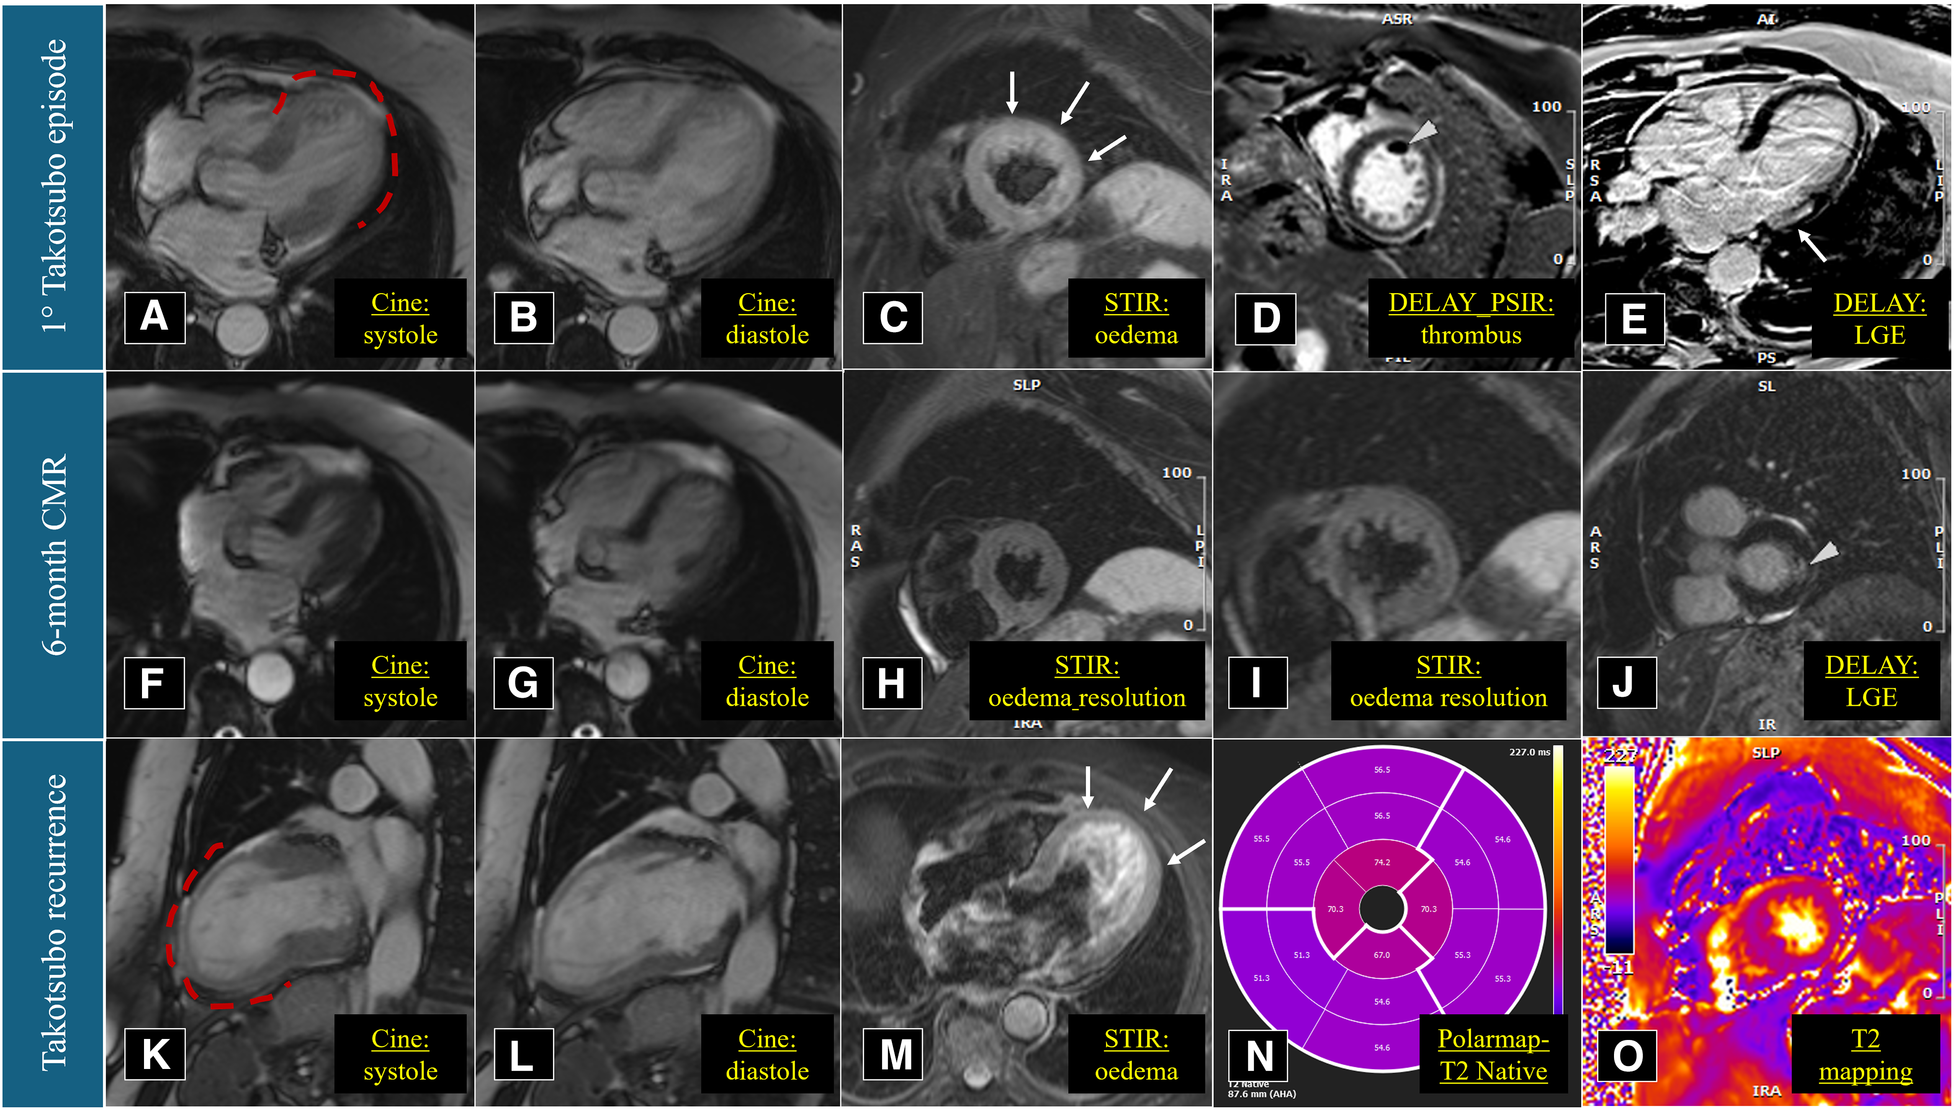

Figure 3

Cardiac magnetic resonance imaging performed in March 2021 (A–E), September 2021 (F–J), and March 2023 (K–O). Red dotted lines underline the apical akinesia during left ventricular systole.

The patient is a 74-year-old woman with type 2 diabetes mellitus, hypercholesterolaemia, mild overweight (25.7 Kg/m2), and a remote undocumented history of myocardial infarction in the infero-lateral wall treated by intravenous fibrinolysis. Back then, no coronary artery disease was found at angiography. More recently, in 2021, she was admitted to hospital with a diagnosis of TTS. In that case, she complained of new onset chest pain following an argument on the phone. The 12-lead ECG showed negative T-waves in the infero-lateral leads (Figure 1A). The coronary angiography documented tortuous epicardial coronary arteries, free from significant lesions, with diffuse slow flow (Figures 2A,B). Hyperkinesia of the basal segments, akinesia of the middle and apical segments, and ejection fraction (EF) of 35% were seen at left ventriculography (Figures 2C,D). White blood cell count was 6,690/mmc (URL 10,000/mmc), peak plasma level of high-sensitive troponin-T was 216 ng/L (female gender URL <10), whereas urinary metanephrines were within normal limits. On day 5, a cardiac magnetic resonance (CMR) confirmed the diagnosis (Figures 3A–E) showing in addition the presence of a small intraventricular thrombotic formation (15 × 8 mm) for which oral anticoagulant therapy was given. Discharge therapy included an angiotensin-converting enzyme (ACE) inhibitor. Oral beta blocker was not prescribed in consideration of the occurrence of significant bradycardia on that drug. The clinical course was uncomplicated and, 6 months after the event, a planned CMR found complete functional recovery of the left ventricle, oedema reduction, disappearance of the intraventricular thrombus, subendocardial late gadolinium-enhancement (LGE) at the basal inferolateral wall level (Figures 3F–J) as a result of remote necrosis. Oral anticoagulation was stopped.

In early 2023, the patient arrived at the Emergency Room complaining of fatigue and chest pain. Since the ECG showed slight QRS widening, left anterior hemiblock, and ST-segment elevation in the lateral leads (Figure 1B), the patient underwent an immediate invasive angiography, which excluded again the presence of coronary artery stenosis and showed the apical ballooning pattern of the left ventricle, as in the previous episode (Figures 2E–H). The diagnosis was recurrent TTS. Research of obvious physical or emotional stress was negative. The only relevant finding was a positive routine swab test for severe acute respiratory syndrome coronavirus-2 (SARS-COV-2), in the absence of fever or respiratory symptoms. The hospital stay was prolonged due to transient QT-segment elongation, but no complications occurred. In consideration of the paucity of data about TTS relapse, the patient performed a third CMR. The imaging pattern was similar to that observed 2 years before: extended akinesia at the level of the middle and apical segments, which appeared diffusely oedematous in the STIR sequences; stable subendocardial LGE with ischemic pattern at the basal infero-lateral wall (Figures 3K–O). We repeated the urinary metanephrine assay which demonstrated a slight, but not significant, increase in normetanephrine. WBC count was 5,450/mmc (URL 10,000/mmc), plasmatic interleukin-6 title was 44.7 pg/ml (URL < 5.9), while high-sensitive troponin-T peak was 386 ng/L (female gender URL <10).